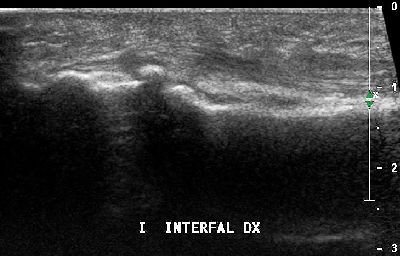

Sesamoide accessorio primo dito interfalangeo (img. 01) Sesamoide accessorio primo dito interfalangeo (img. 01)

Sesamoide accessorio primo dito interfalangeo (img. 02) Sesamoide accessorio primo dito interfalangeo (img. 02)